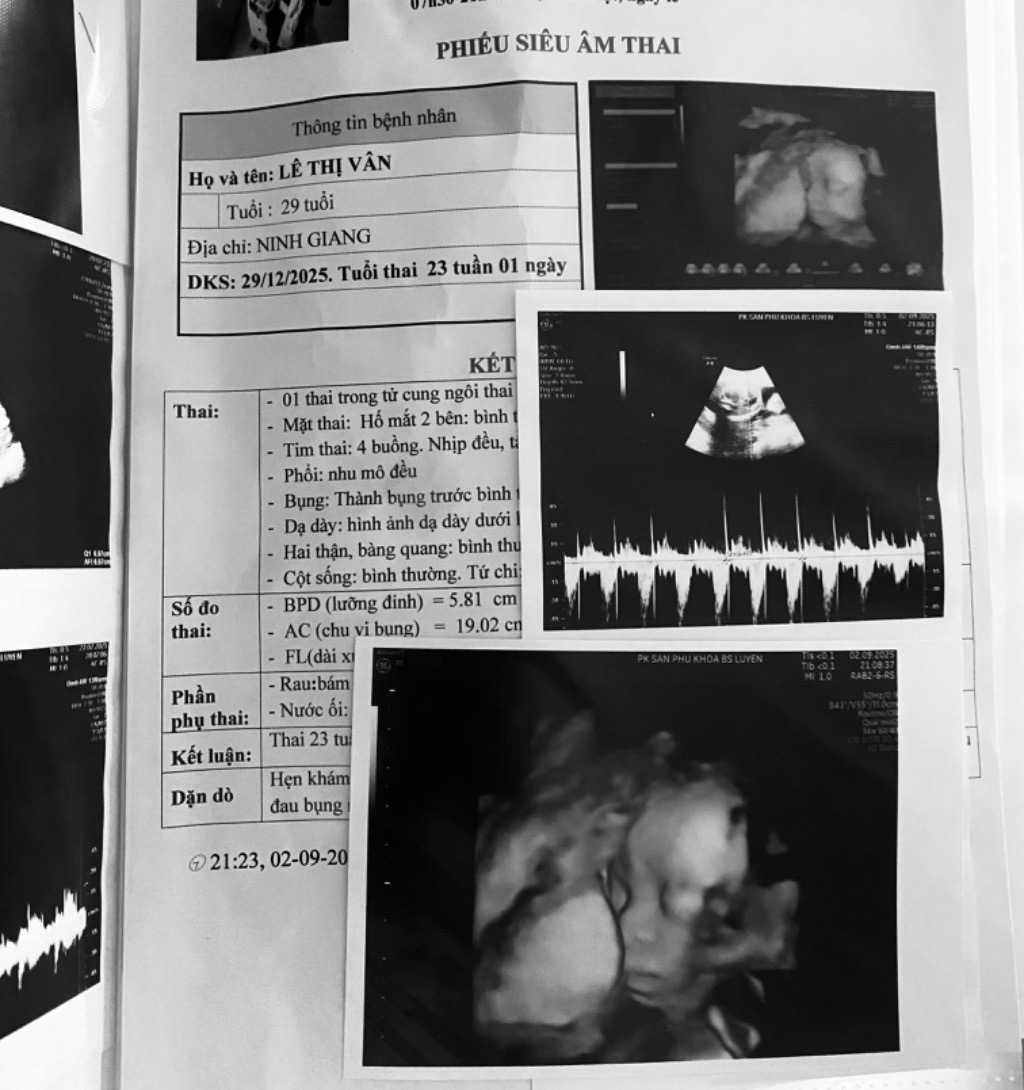

Lê Thị Vân